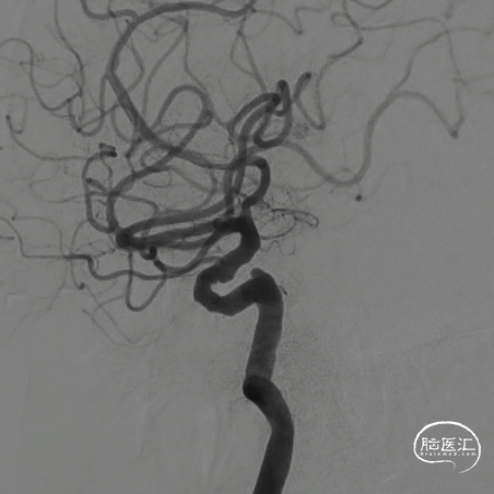

右侧颈动脉造影:海绵窦、眼段动脉瘤。

左侧颈内动脉造影:颈内动脉起始部中度狭窄,海绵窦段、床突上段多发动脉瘤。

选取良好工作角度。

导管顺利到位。

术后3D造影及支架重建,可见支架展开和贴壁良好。